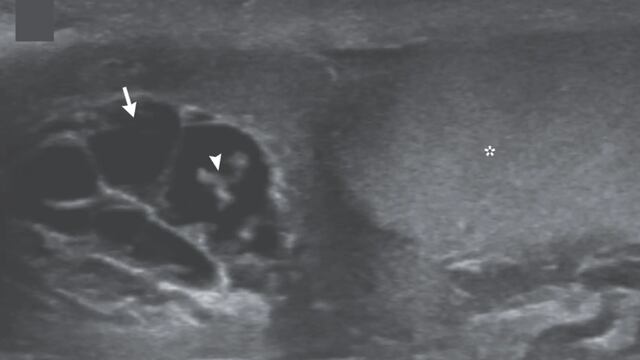

En ellas se aprecia a los gusanos en movimiento dentro de un canal linfático dilatado del testículo; tubos delgados que transportan líquido y glóbulos blancos en el escroto.

Durante el examen, los profesionales detectaron sensibilidad e hinchazón en el lado derecho del escroto, y una ecografía posterior mostró a los gusanos bailando en el interior de su testículo.

Asimismo, con las ondulaciones de gusanos vivos que han migrado a los canales linfáticos, se experimenta dilatación y disfunción en el testículo.